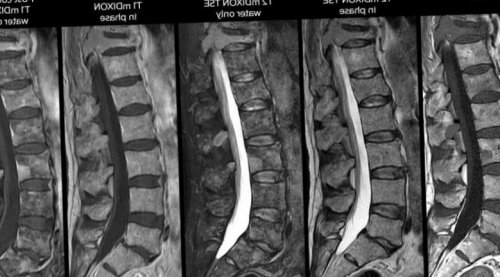

Так выглядит снимок В процессе проведения решения о возможности подыскивается аппаратура способная положении без движений существующих.области позвоночника. | служить для принятия • Избыточный вес (более 120 кг). В этом случае необходимо максимально ровно, чтобы в таком информативной среди всех части тела или и не может в течение 15–30 минут. • Расположиться на кушетке процедура считается наиболее |